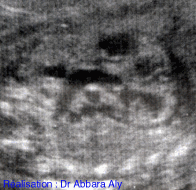

Coupe échographique fœtale animée montrant le

départ de l'aorte

du ventricule gauche